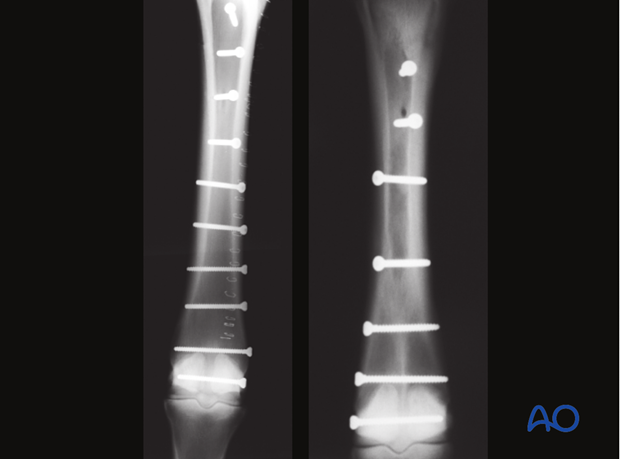

4.5 mm cortex bone screws are placed in lag fashion perpendicular to the fracture plane that is been exposed. The screws should be approximately 3-5 cm apart and a considerable effort should be made to keep the screws in the center of each fragment.

Screws should NOT be placed if the fracture plane cannot be identified. The arrangement of the screws will vary according to the specific configuration of the fracture.

The completed fixation is confirmed radiographically.